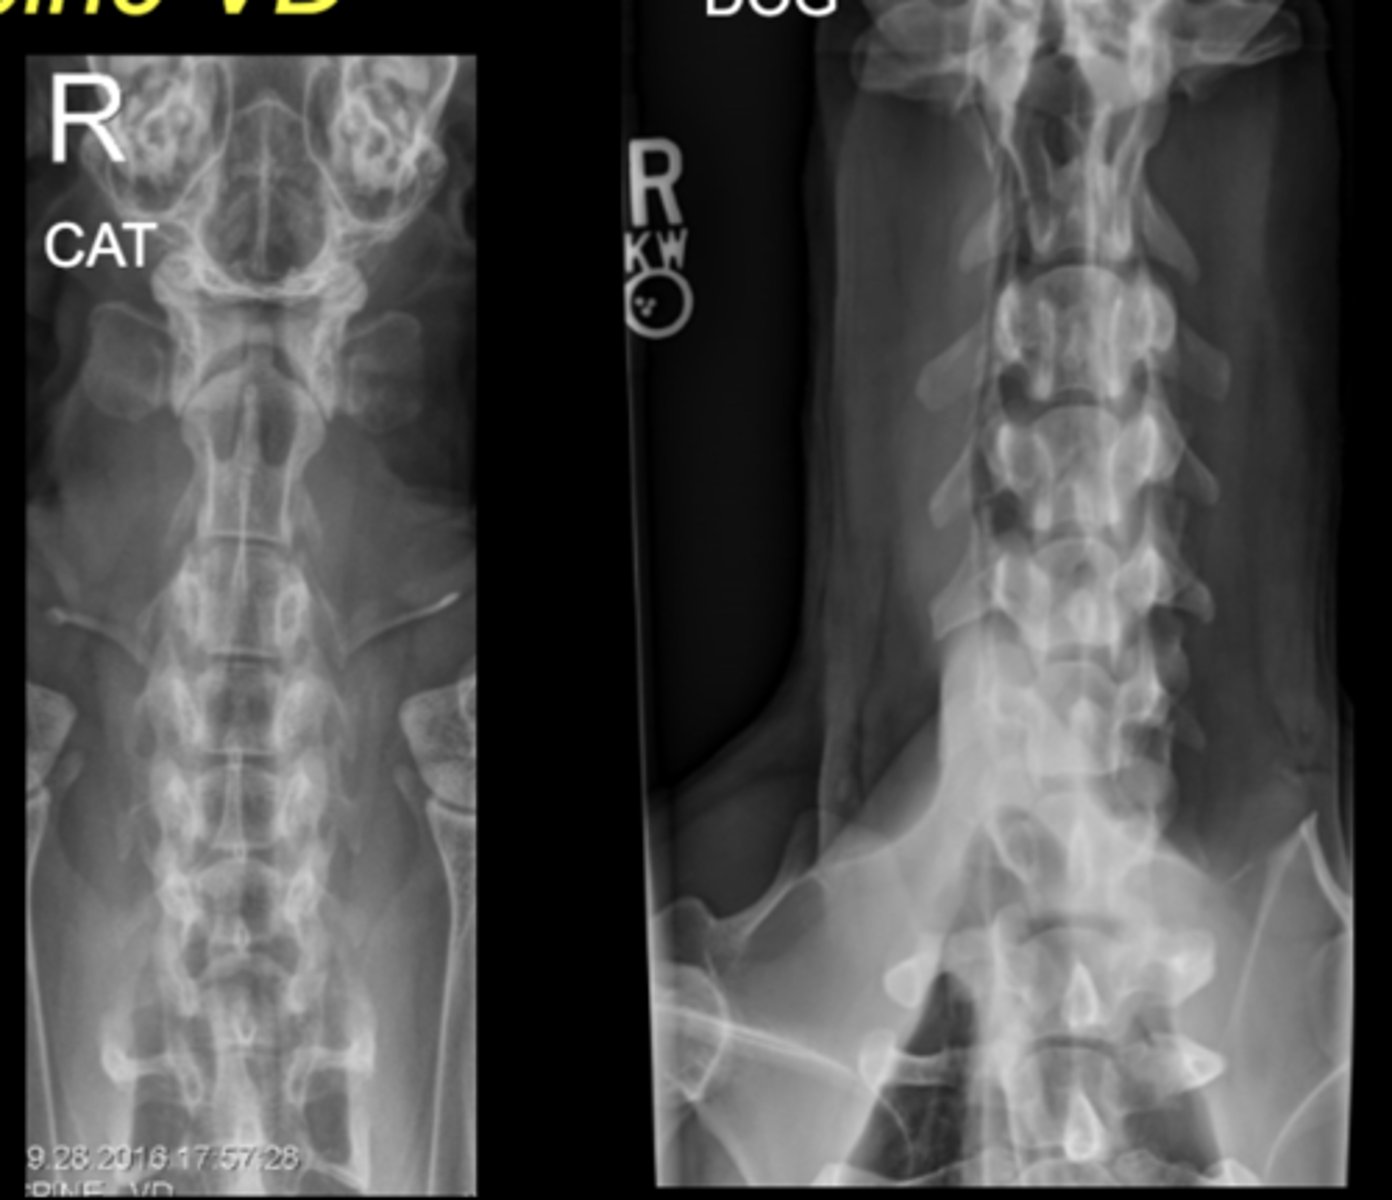

SM Animal Spine Lateral

SM Animal Spine VD